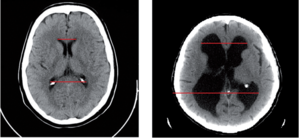

13.2.2. Anatómiai vonatkozások (2–3. ábra)